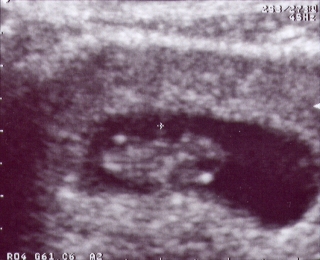

Here's my first picture. The technician is estimating that I am 8 weeks along at this point. I'm pretty small, but I'm growing fast. |  This is me at 12 weeks. Now you can see some of my body parts. It looks like I'm upside down because I am facing Mommy's back. I was too camera shy to turn around. I am just over 6 cm long -I still have a lot of growing to do to catch up to my big sister. |